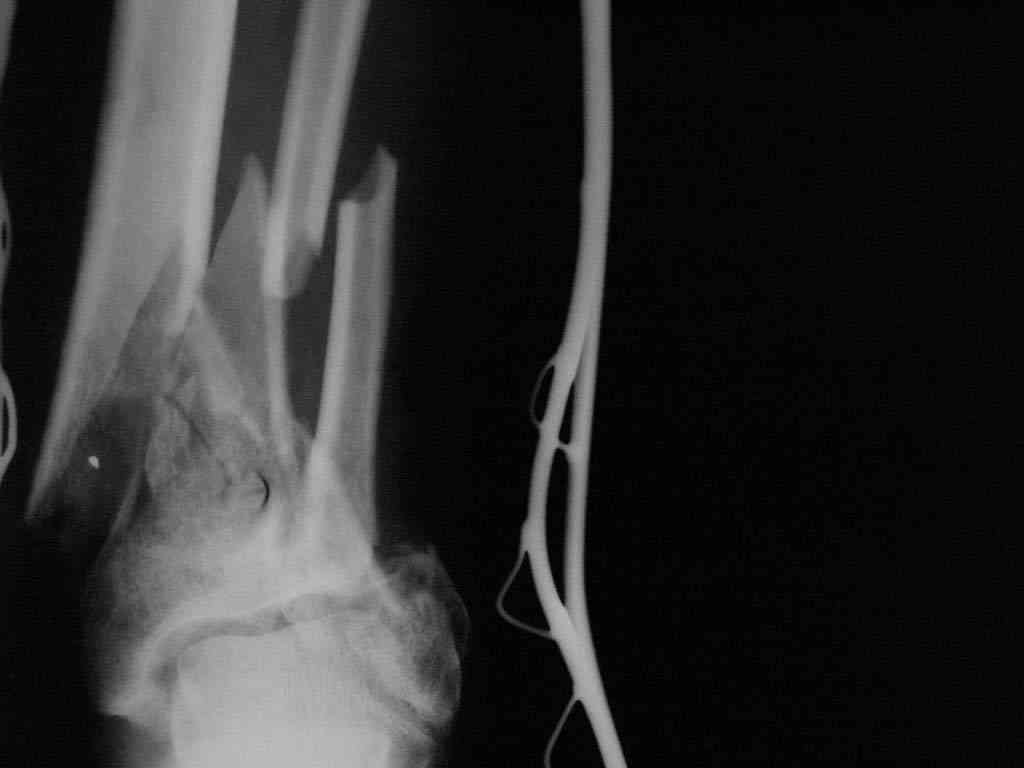

|  |  |  |  status localis на 14.11.08 (В ране визуализируется сухожилие.) | Больной А, 40 лет, находится в клинике с 15.10.08 с диагнозом: Сочетанная травма. Ушиб головного мозга лёгкой степени тяжести. Компрессионные переломы тел 12 грудного и 5 поясничного позвонков без неврологических осложнений. Закрытый внутрисуставной многооскольчатый перелом дистальных метаэпифизов обеих костей правой голени со смещением. Открытый внутрисуставной многооскольчатый перелом дистальных метаэпифизов обеих костей левой голени со смещением (см. Р-граммы). Хронический алкоголизм. Доставлен СМП после падения с 5-го этажа (не суицид). При поступлении состояние тяжелое. Глубокое оглушение. Дыхание самостоятельное, адекватное. Гемодинамика стабильная. По внутренней поверхности левой голени, в нижней трети, рвано-ушибленная рана 10-6 см, из раны выстоит проксимальный отломок большеберцовой кости, рана обильно загрязнена землёй. Интенсивная терапия в условиях реанимационного отделения, вытяжение за правую пяточную кость, параартериальная блокада обеих нижних конечностей, гипсовая лонгета на левую нижнюю конечность, ас-повязка на рану. Через 4 часа после поступления оперирован: после неоднократного промывания раны тёплой проточной водой с мылом, антисептиками, при ревизии определяется земля в канале проксимального отломка на глубину 3 см..., отсутствие надкостницы на концах дистального и проксимального отломков на 3 см. Удалено значительное количество мелких костных фрагментов, перемешанных с землёй, выполнена ПХО раны, резекция проксимального конца большеберцовой кости на 3,5 см, ЧКДО аппаратом Илизарова. Рана не ушивалась. В последующем перевязки раны с "Левомеколь", через 3 недели с момента травмы в ране определялись грануляции, нежизнеспособный конец дистального отломка. 10.11.08 ВХО раны, резекция дистального отломка на 3 см, перемонтаж аппарата наружной фиксации (см. Р-граммы). Отломки сближены на 2 см (остеотомию малоберцовой не делали). В настоящее время (5 сутки после операции) незначительное количество серозного отделяемого из раны, имеется дефект кости 4 см (см. Р-граммы). В последующем склоняемся к перемонтажу аппарата наружной фиксации, остеотомии малоберцовой кости в области повреждения, сближении отломков. По заживлению раны удлинение левой голени на 4 см. Однако, некоторыми высказывалось мнение о необходимости артродеза. Представляем рентгенограммы левой голени при поступлении, после повторного оперативного лечения и фото st.localis на 14.11.08. Будем очень благодарны за критику, комментарии, пожелания и мнения о дальнейшей тактике лечения.

Рентгенограммы прилагаются. Фото местного статуса выложу в ближайшее время.

Мы обычно не фиксируем малоберцовую кость. Просто стараемся сопоставить ее концы за счет хорошей репозиции. В представленном случае имеется некоторое смещение дистальных фрагментов кнаружи, и, как мне кажется, ротация их вместе со стопой кнутри (ротация хорошо заметна на прямом снимке по форме таранной кости и на боковом по соотношению отломков малоберцовой). Если это действительно так, то это несложно сейчас постепенно устранить в аппарате. И тогда концы малоберцовой кости будут находиться поближе друг к другу.